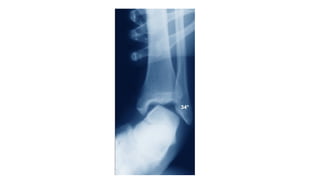

Evaluación Rx

- AP, Lateral y proyección de mortaja

- Evaluar ensanchamiento de la mortaja

- La distancia entre el borde lateral del maléolo

medial y el astrágalo, y la distancia entre la

cúpula astragalina y la superficie articular tibial

distal deben ser similares